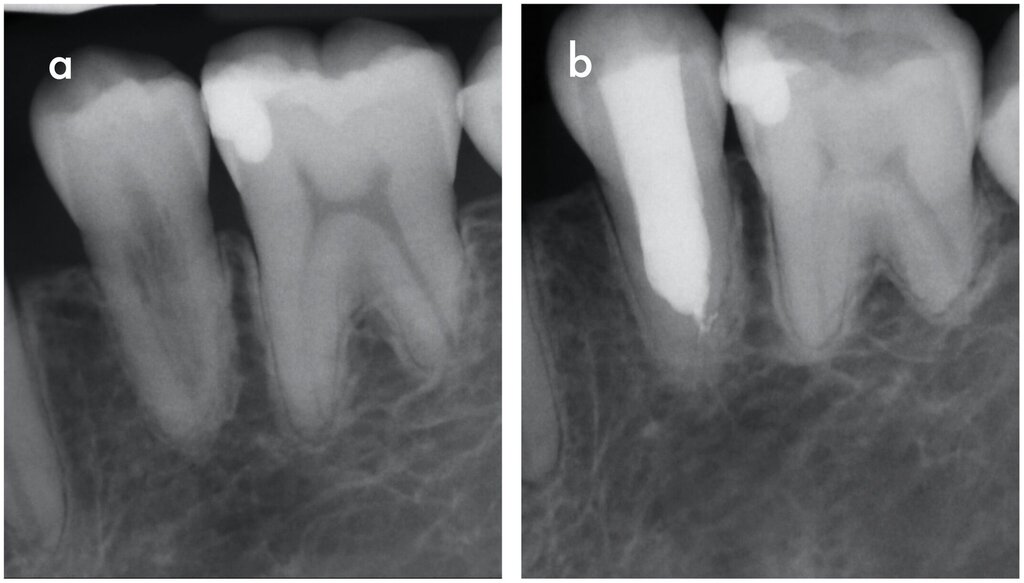

Die entzündliche Resorption wird durch Bakterien aus der nekrotischen koronalen Pulpa stimuliert und durch vitales Pulpagewebe apikal der Resorptionsfront aufrechterhalten (Abbildung 4a). Zusätzlich findet sich Granulationsgewebe im Inneren der Zahnwurzel. Wenn zusätzlich zu diesem Granulationsgewebe knochenähnliches Reparaturgewebe gebildet wird, spricht man von interner Ersatzresorption (Abbildung 4b). In beiden Fällen können je nach Pulpastatus Schmerzen auftreten. Radiologisch stellt sich die entzündliche interne Wurzelresorption meist als ovale oder zirkuläre, ballonartige Aufhellung des Wurzelkanals dar, während die Ersatzresorption ein unregelmäßiges, wolkiges und oft unscharf begrenztes Erscheinungsbild zeigt [Nilsson et al., 2013; Patel et al., 2010]. Es ist zu beachten, dass externe invasive zervikale Resorptionen (siehe unten) bei entsprechender Projektion häufig als interne Resorptionen fehlinterpretiert werden.

Eine Sonderform interner Wurzelresorptionen tritt im Rahmen von Reparaturvorgängen nach intraalveolären Wurzelfrakturen auf. Diese verlaufen häufig transient (Abbildung 4c). Eine klinische Symptomatik ist in der Regel nicht vorhanden, radiologisch lassen sich jedoch transiente Umbauprozesse entlang der Frakturlinie nachweisen [Andreasen, 2003; Andreasen und Andreasen, 1988].